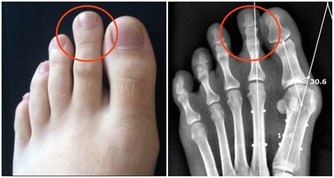

7. 與醫生建立良好關係

降低風險和並發症的一個好方法是,與你的醫生建立良好的關係。通常情況下,他會將你轉介給其他醫生:眼科醫生,足病醫生,心髒病專家,內分泌科醫生等。接受相關健康檢查,有助於採取預防措施,減少糖尿病並發症。